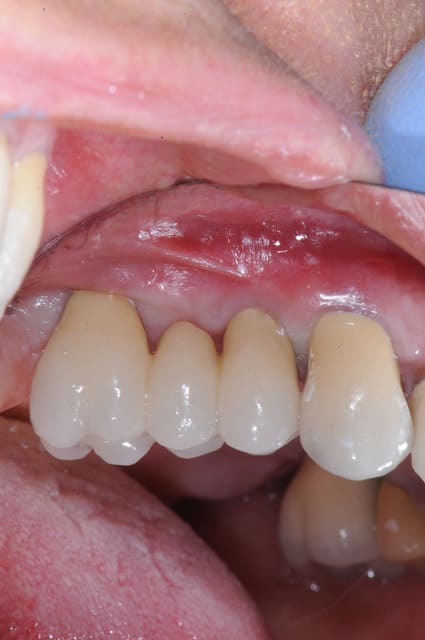

voici pou la cicatrisation à j+4mois avant la pose des implants et la dépose des vis

et après 3 mois après pose des implants puis pose du bridge